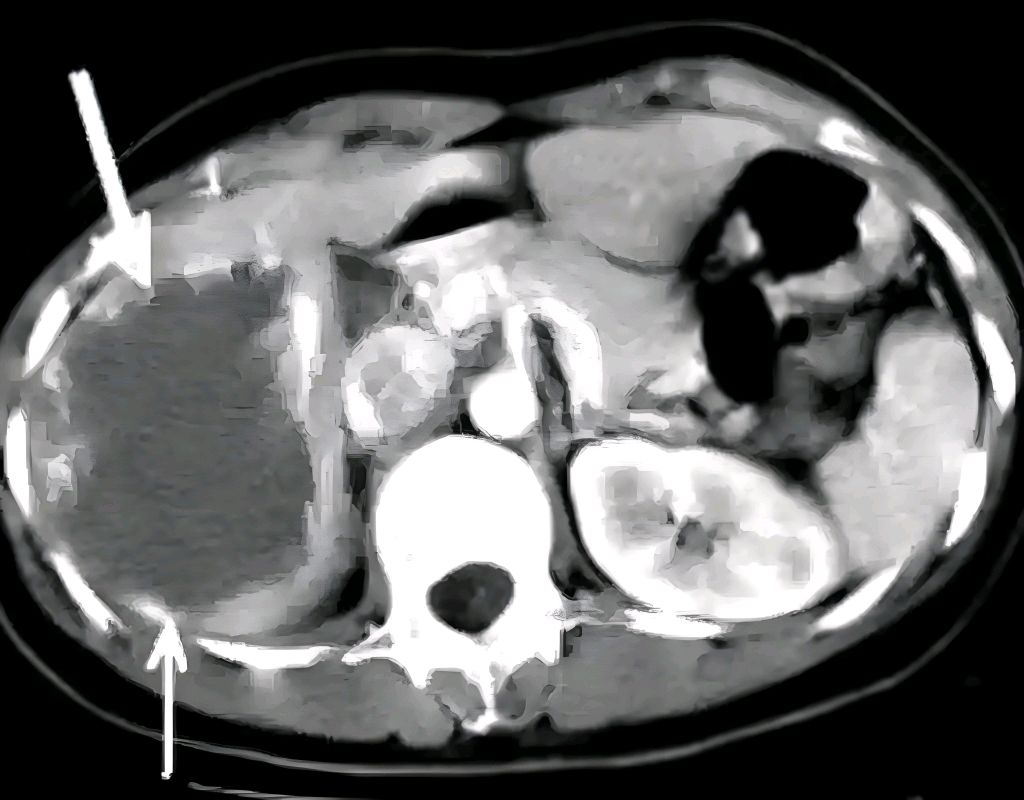

2. 增强CT或MRI:能清晰显示血管瘤特征(如“早出晚归”的强化模式)。

医生会结合检查结果排除肝癌、肝囊肿等疾病,避免误诊。